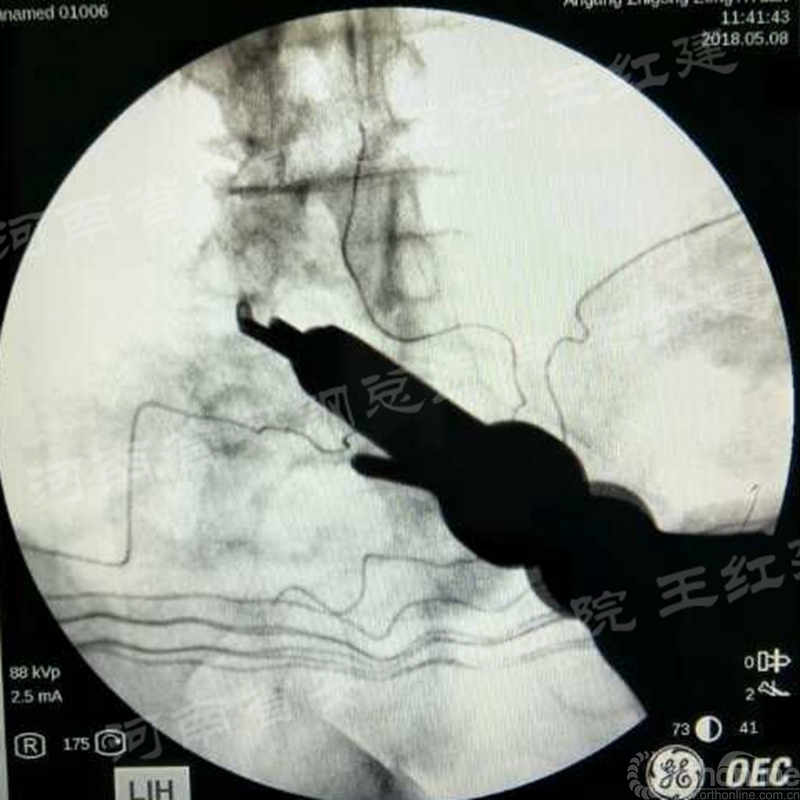

在固定的步骤可以先期进行经皮螺钉置入,再进行融合器的置入,进而实现充分固定。

椎弓根植入加压固定

单边椎弓根植入加压固定

双侧椎弓根植入加压固定

手术步骤:先期经皮螺钉置入、再进行融合器的置入